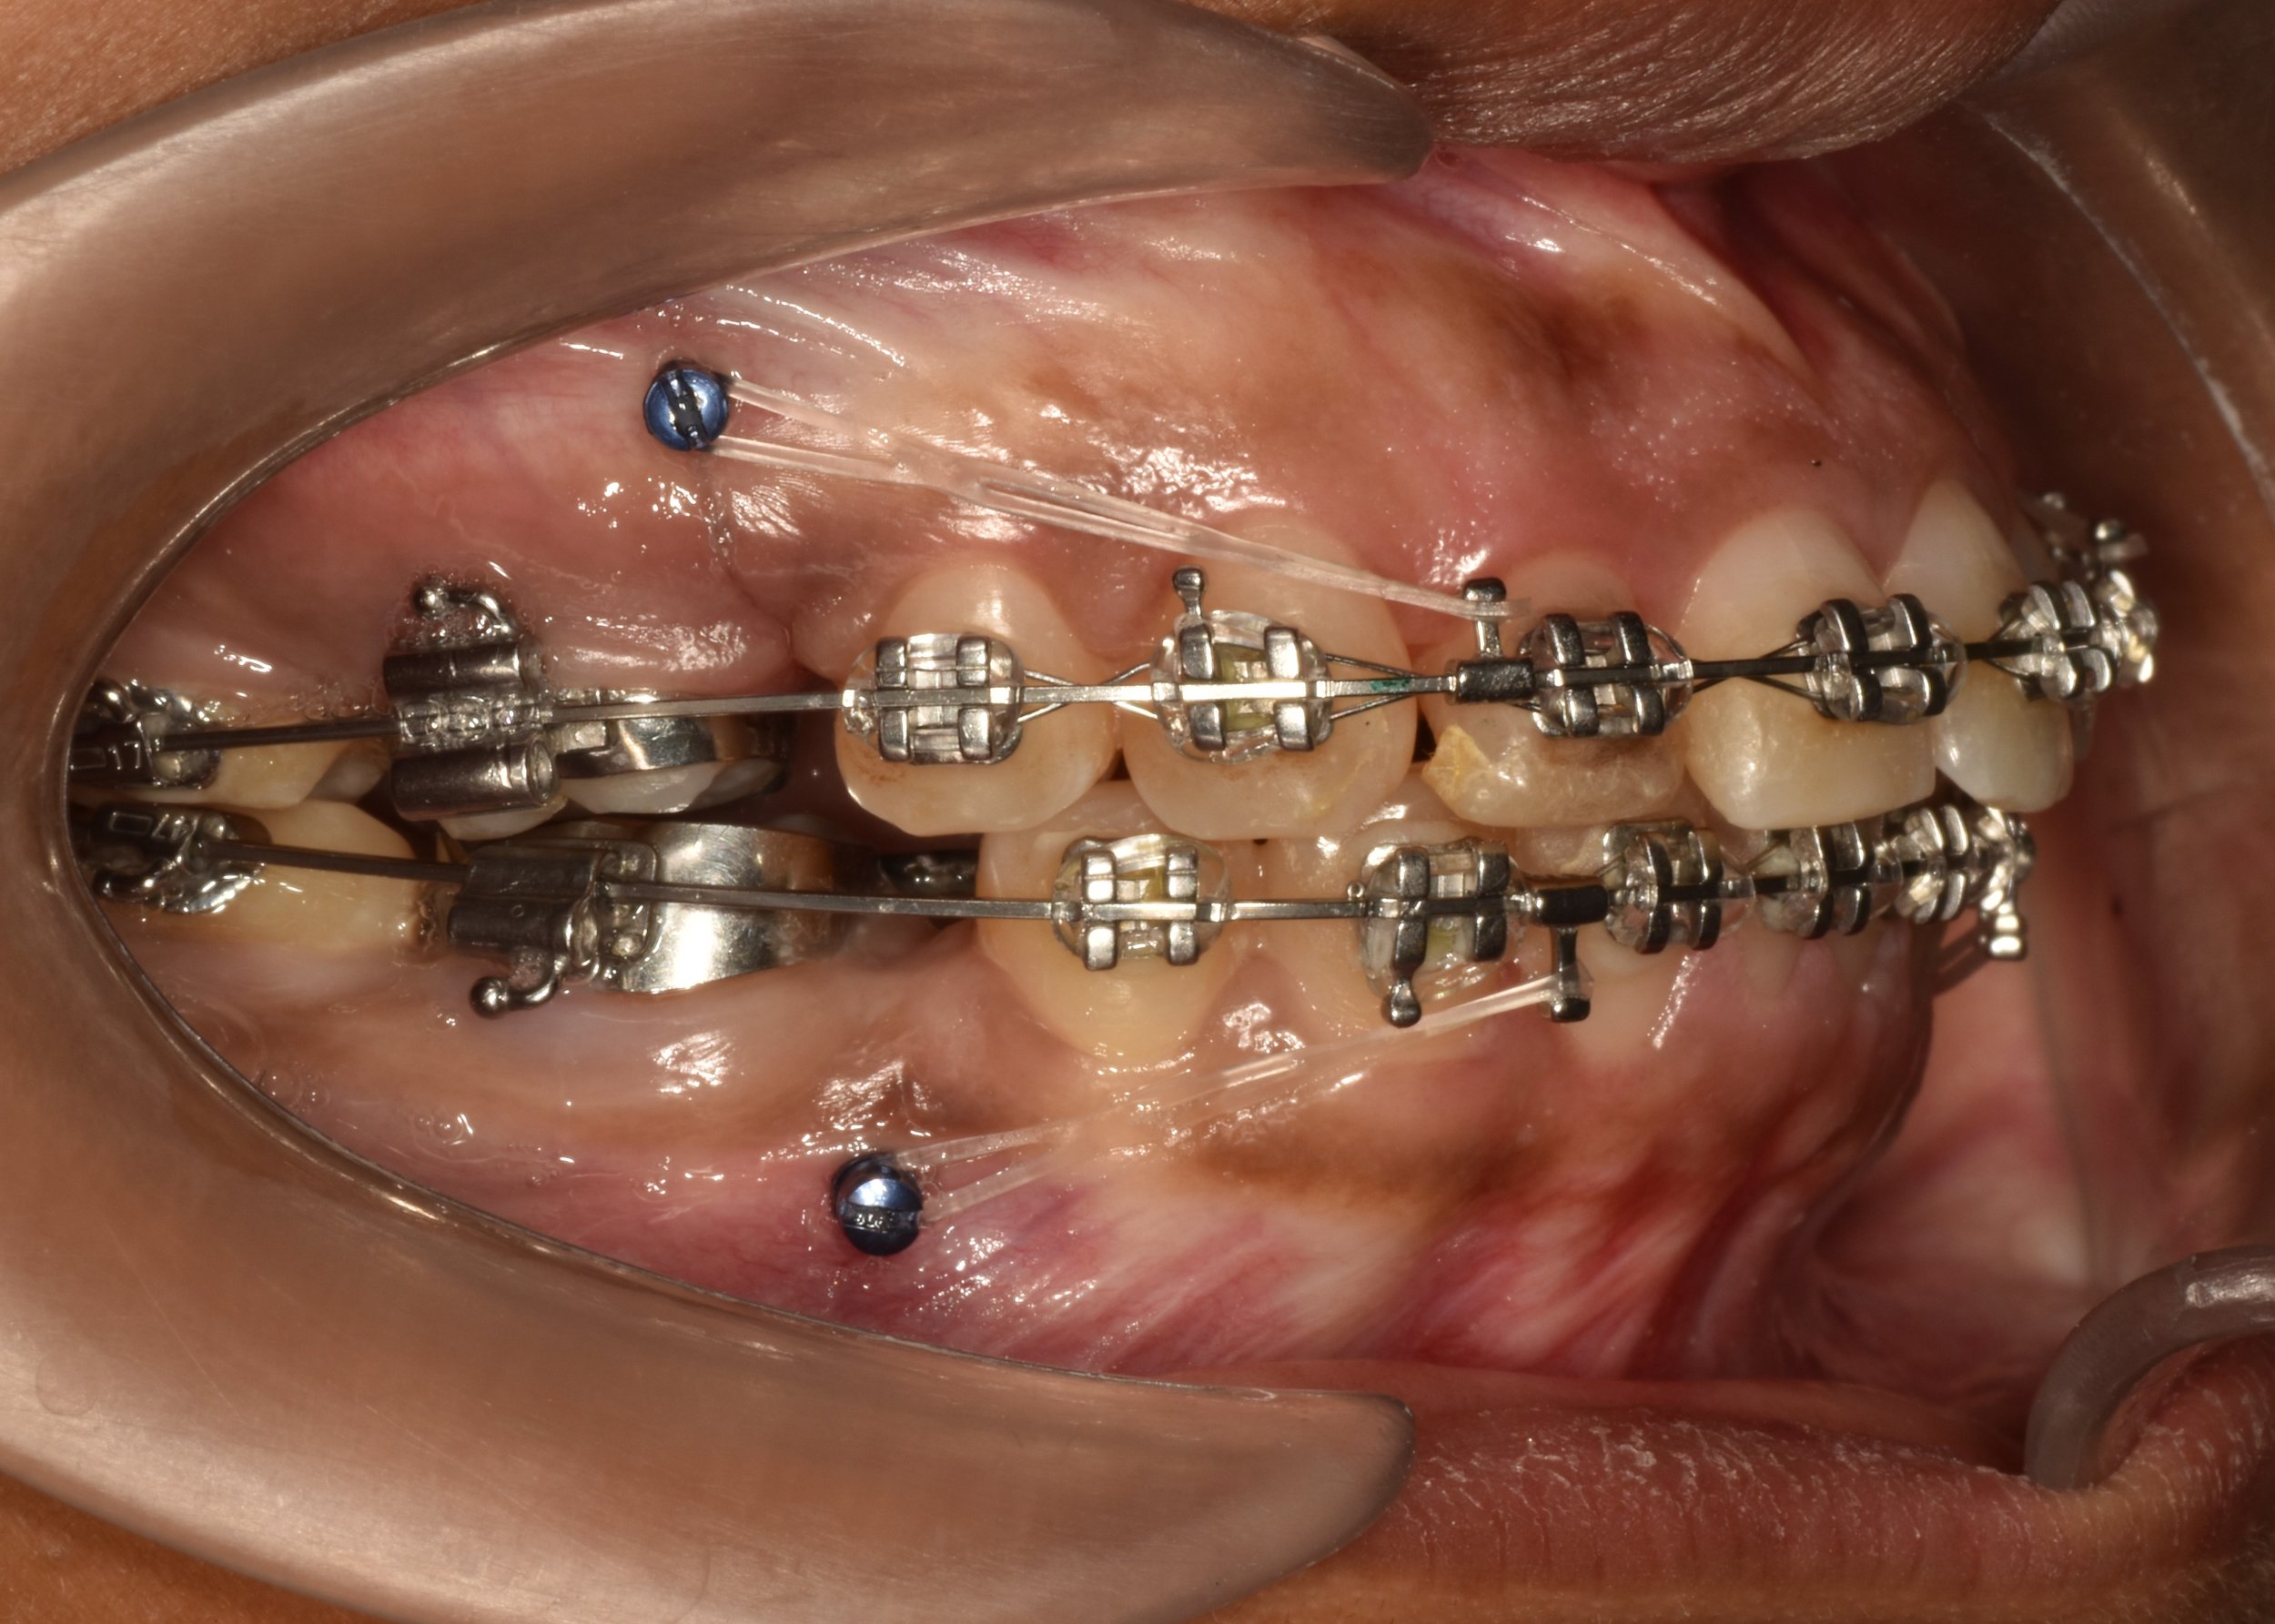

Extra-radicular implants